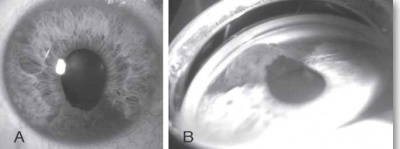

ההסתמנות השכיחה ביותר של המחלה בעולם המערבי היא הופעה של אישון לבן (תמונה 6), ובמקום השני - פזילה. בארצות מתפתחות בלט עין הוא הסתמנות יותר שכיחה של המחלה, ומקורה, קרוב לוודאי, באבחנה מאוחרת של המחלה.

הגרורות העיניות צומחות במהירות ומסכנות את הראייה, לכן אבחנה מהירה וטיפול מתאים חיוניים לשמירה על איכות חיי המטופל. האבחנה של מוקד גרורתי היא קלינית בעיקרה, ומתבססת על אנמנזה ובדיקה ללא צורך בביופסיה. בבדיקת עיניים יתגלה נגע מורם בגוון קרמי או צהוב חיוור, המלווה בנוזל תת-רשתי[23] (תמונה 5), בקוטר מקסימלי ממוצע של 9 מילימטר ובעובי ממוצע של 3 מילימטר[26]. בכשליש מהמקרים יופיעו מספר מוקדים גרורתיים בעין[16]. יש לציין כי יש גידולים השולחים גרורות בעלות מראה ייחודי ואופייני; למשל קרצינומה של בלוטת התריס וקרצינואיד נוטים לשלוח גרורות בעלות גוון כתום אופייני.